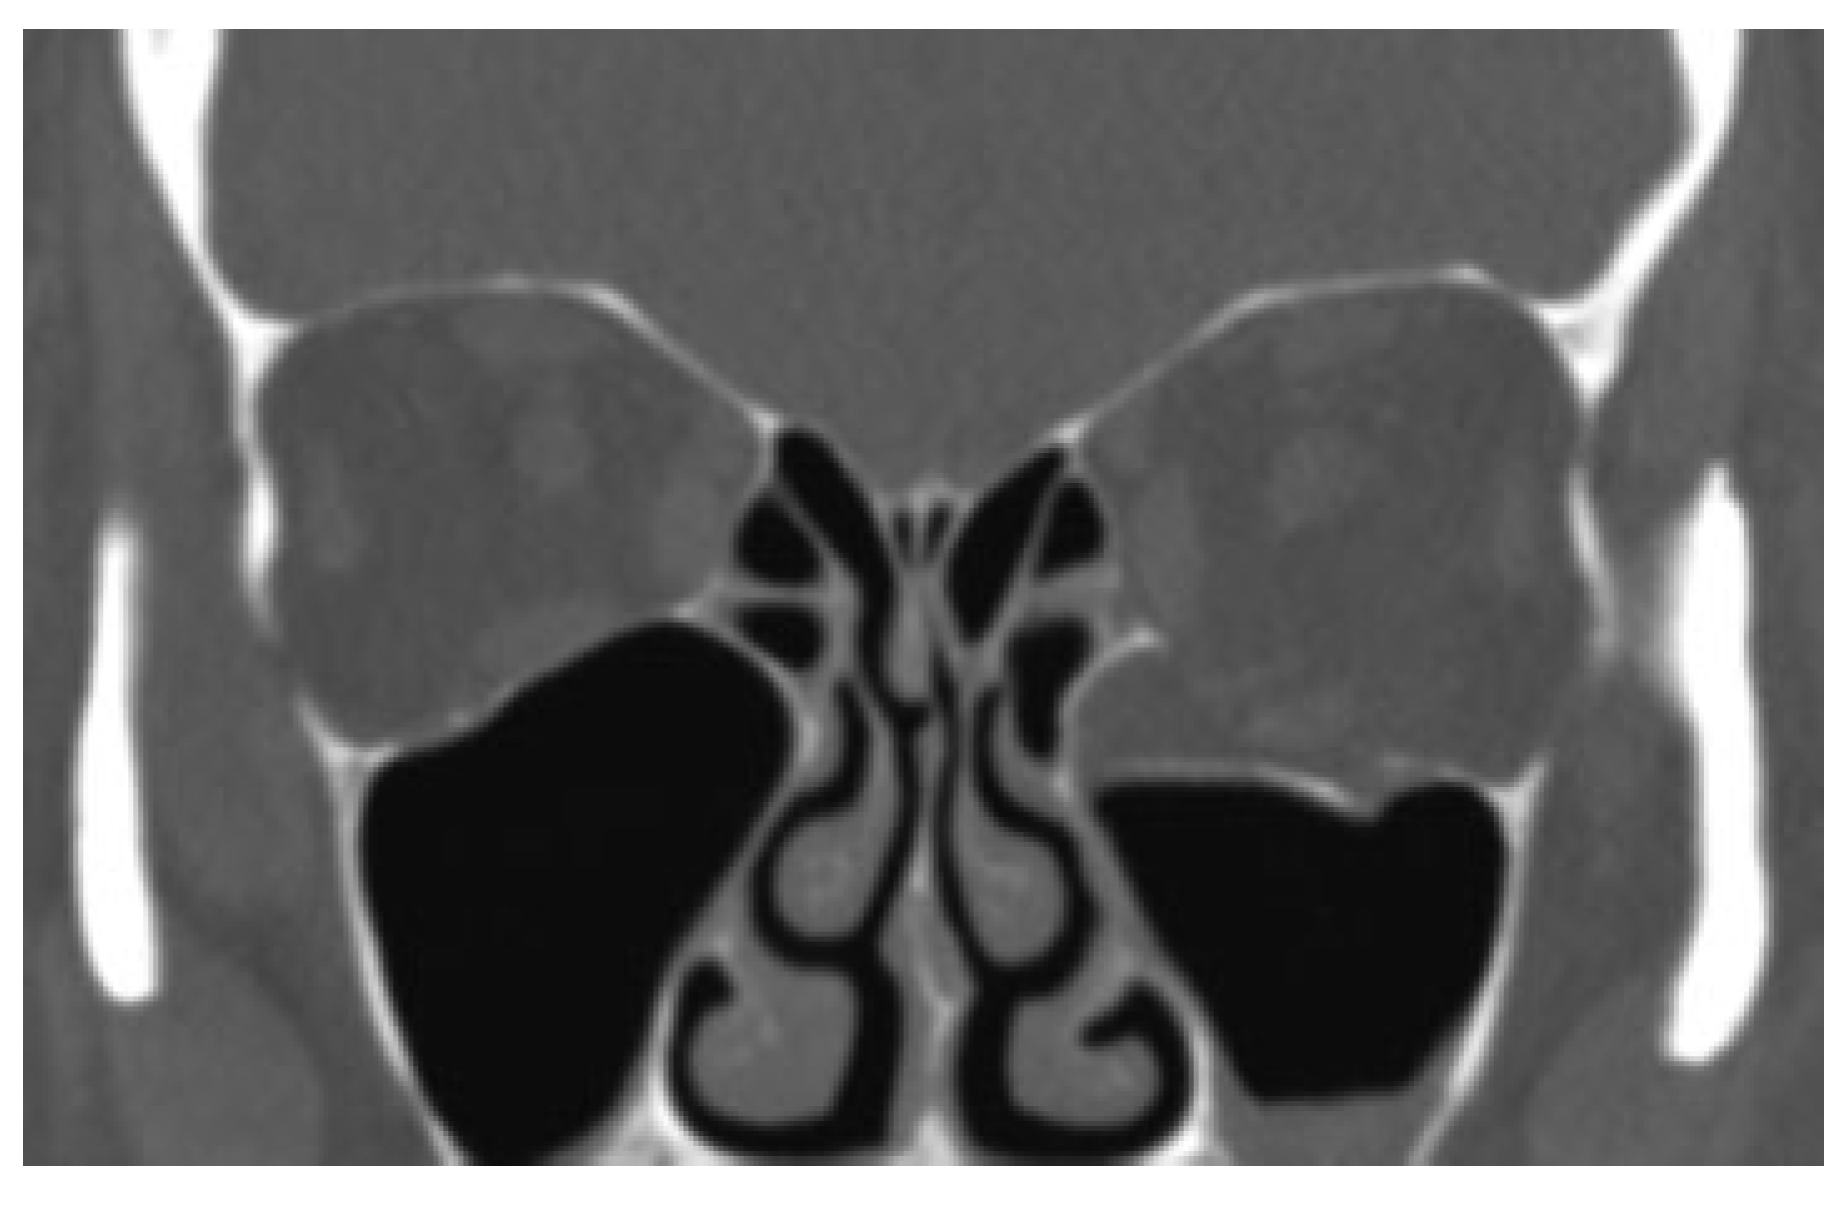

A 59-year-old female presented to the maxillofacial outpatient department following a mechanical fall resulting in a left orbital floor fracture. Enophthalmos of 2 mm was present and a CT scan revealed a large floor defect (Figure 2 and Figure 3). Diplopia was present on upward gaze. A rapid prototyping model was fabricated and a Synthes titanium orbital plate was further adapted preoperatively. The orbital floor was accessed via a mid-lid approach and the modified titanium orbital plate was inserted. No further adaptation of the plate was required and the time taken from insertion of the plate to final fixation was less than 1 minute, as no further adaptation was necessary. Position was confirmed with an intraoperative CT scan (O-arm, Medtronic [Medtronic, Minneapolis, MN]) (Figure 4, Figure 5 and Figure 6). The patient’s diplopia and enophthalmos had resolved 2 weeks postoperatively and no complications were noted at the 6th week follow-up.

Figure 2.

Coronal section of orbital floor fracture in Case 1.